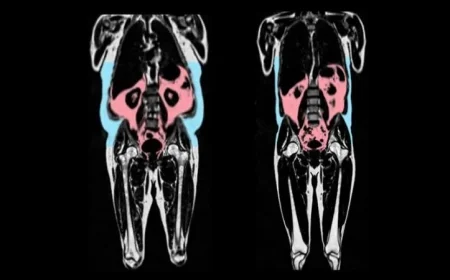

إطلاق تجربة مبتكرة في جامعة كاليفورنيا لفحص سرطان الثدي...

تجربة سريرية لدراسة تأثير الذكاء الاصطناعي في فحص سرطان الثدي تقوم جامعة كاليفور...